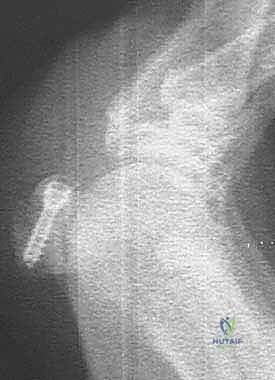

الغوص العميق: جراحة التثبيت الداخلي الدقيق للعظم السمسمي (التقنية الجراحية)

تُعد جراحة التثبيت الداخلي للعظم السمسمي (Internal Fixation of Sesamoid Bone) واحدة من أدق وأعقد جراحات القدم، وتتطلب جراحاً متمرساً في الجراحة المجهرية مثل الأستاذ الدكتور محمد هطيف. الهدف من الجراحة هو إعادة شظايا العظم إلى مكانها التشريحي الدقيق وتثبيتها ميكانيكياً لتسهيل الالتئام الطبيعي، مع الحفاظ على الأنسجة الرخوة المحيطة.